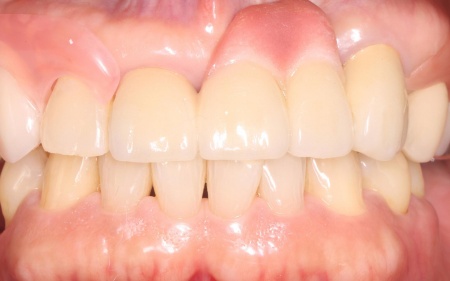

・取り外し式の部分入れ歯

金属製のバネ「クラスプ」を使用せず、やわらかい樹脂素材で作製する入れ歯「バルプラスト」で欠損部を補う方法

メリット:審美性に優れており、装着しても目立ちにくい

デメリット:インプラントと比べると安定感に違いが出る場合がある。快適に使用するためには定期的な調整が必要

患者様は当初インプラントを希望されたものの、治療期間が長くなることから「まずは入れ歯で様子をみたい」とバルプラストによる治療を選択されました。

まず、感染の拡大を防ぐために右上犬歯の抜歯を行い、歯ぐきや骨が安定するまで一定期間経過を観察します。

十分な治癒を確認したうえでお口全体の型取りを行い、技工所で入れ歯を作製しました。

後日、完成した入れ歯を患者様のお口に合わせて細かく調整し、装着時の違和感や噛み合わせに問題がないかを丁寧に確認して、治療を終了しました。